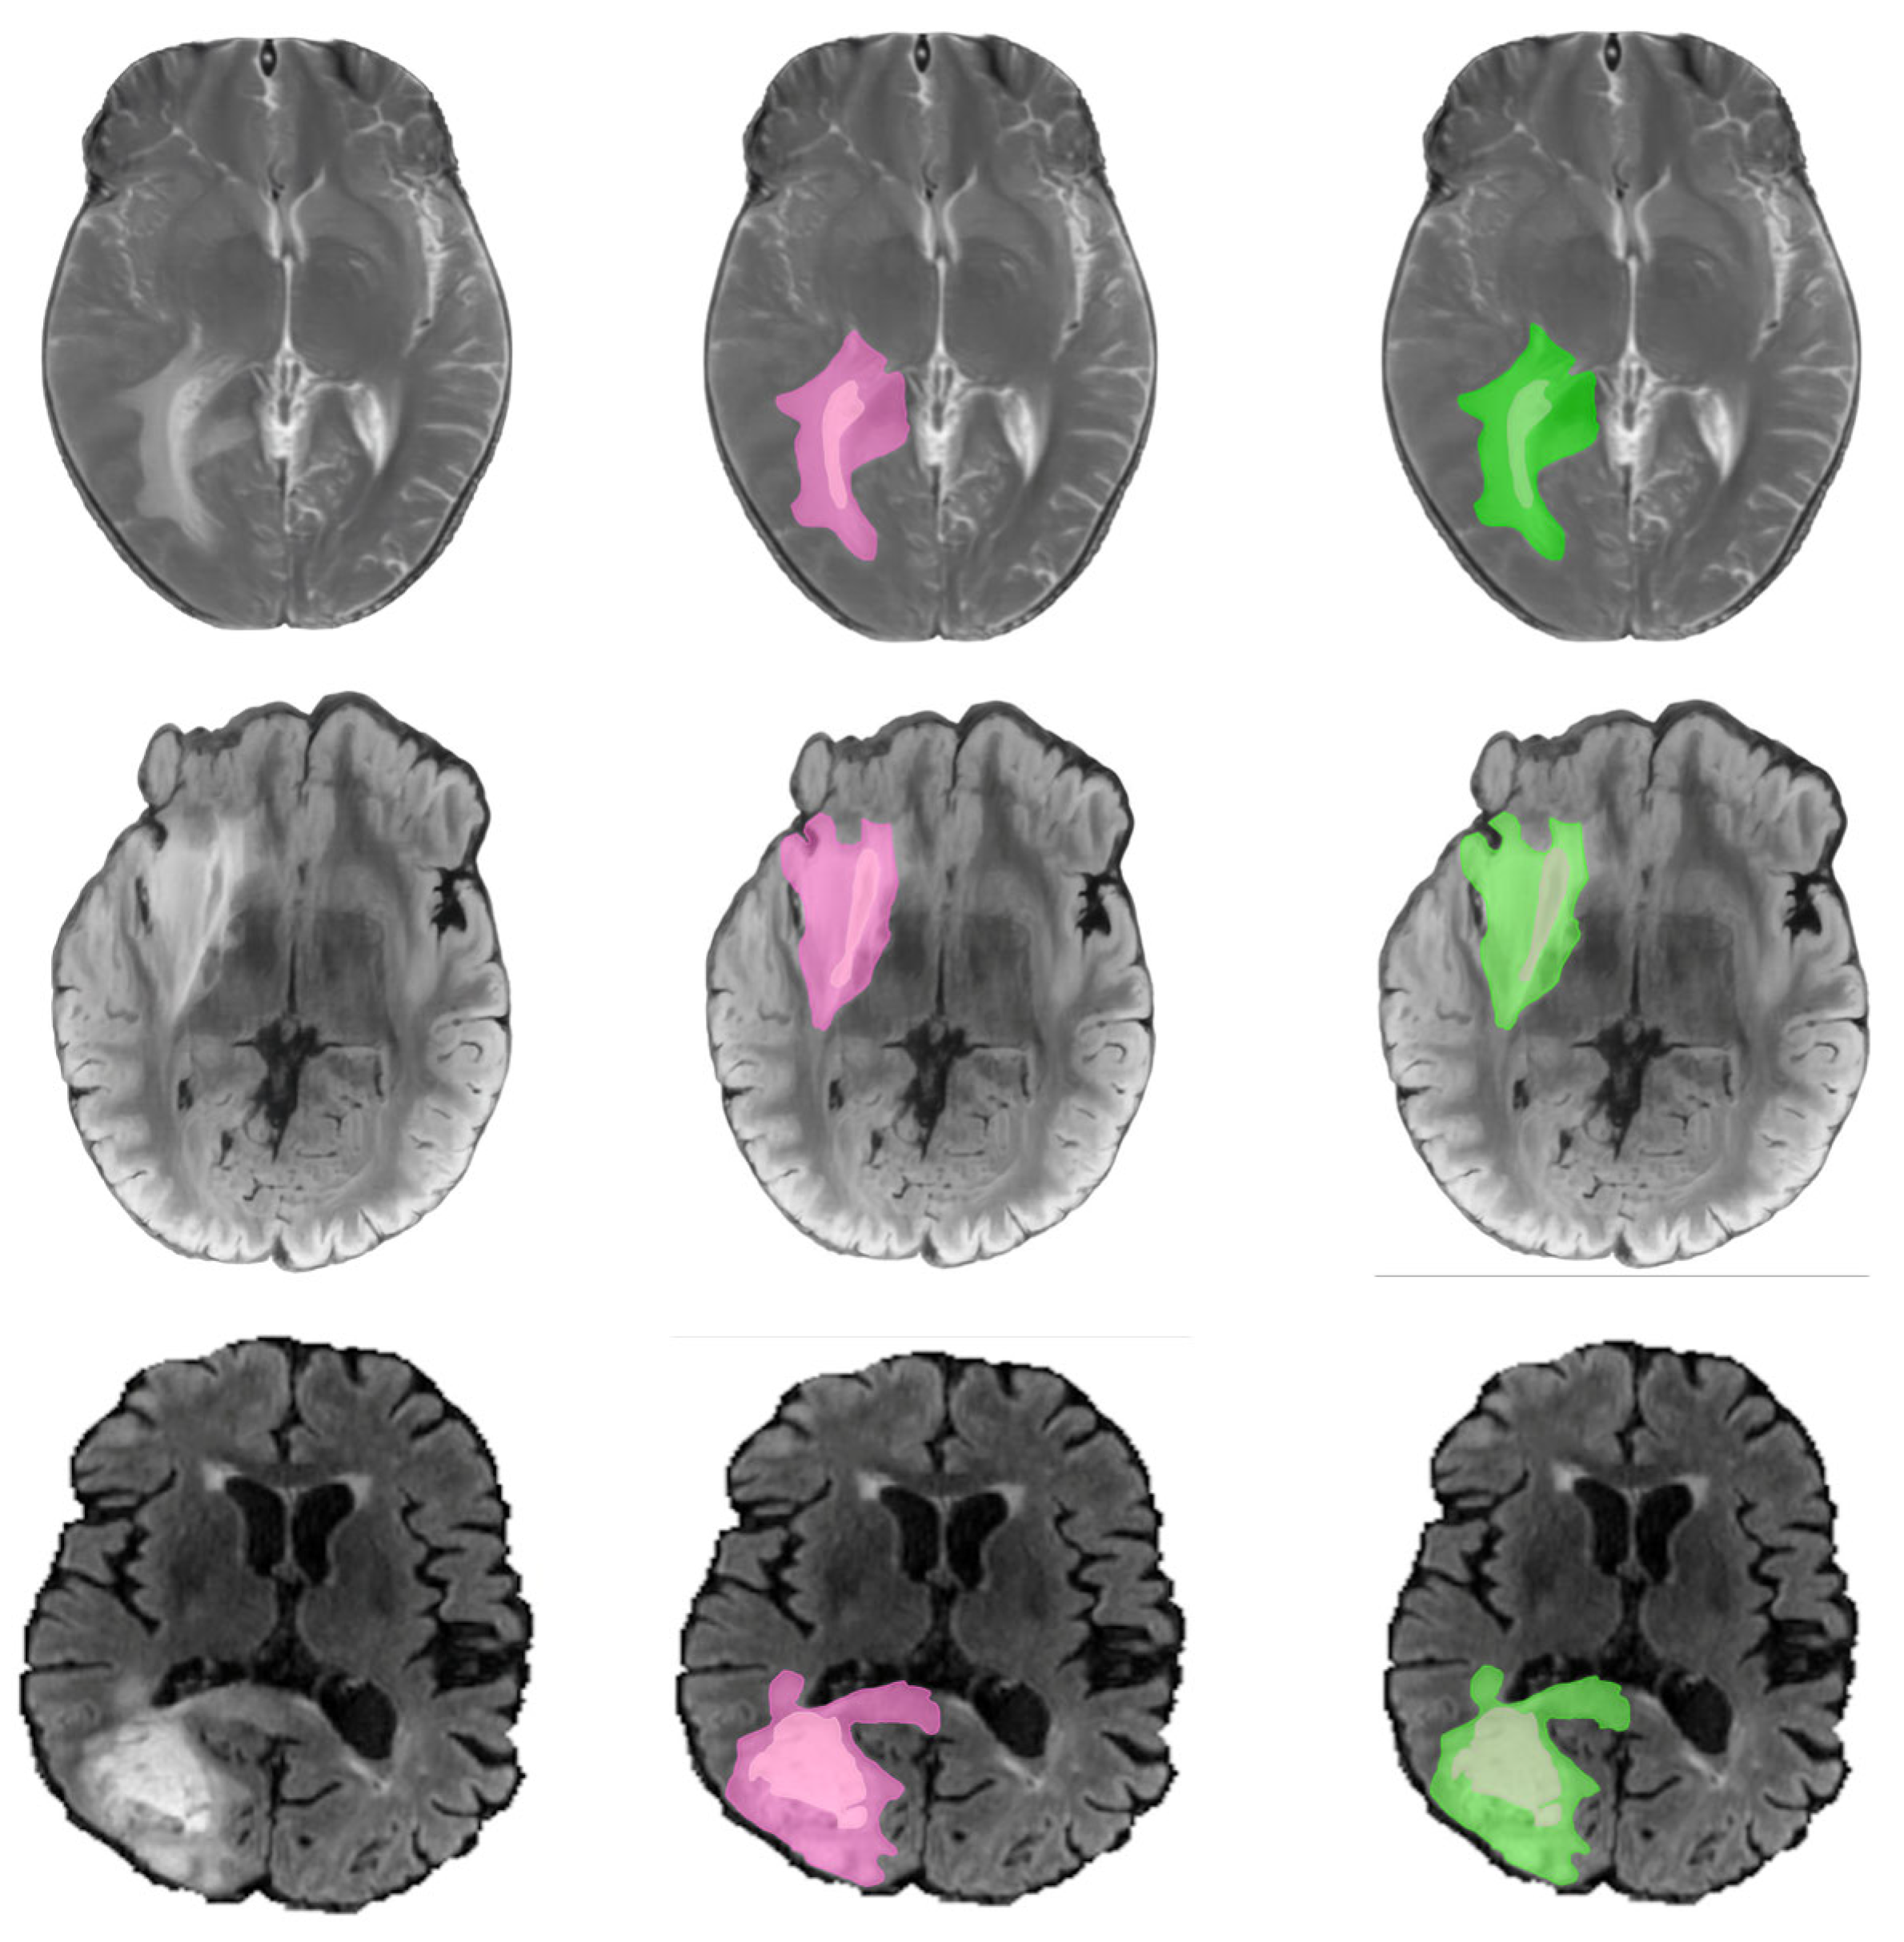

Such evaluation metrics, when combined, establish a strong framework for gauging the effectiveness of the CT-UNet model in terms of accuracy, consistency, and the ability to generalize. Utilizing these metrics, the research and medical communities are able to fully grasp the advantages and drawbacks of the model, thus paving the way for further refinements and exploits in the clinical domain Figure 3.

5. Comparison with Prior Work

The improvements brought by the CT-UNet model in brain tumor segmentation performance have been both quantitatively and qualitatively evaluated through comparison with popular baseline models. This part outlines comprehensive results that are well-illustrated with tables and graphs, revealing how CT-UNet advances different essential metrics.

For a fair comparison, the performances of each model were checked on an identical test set from the BraTS dataset. CT-UNet surpasses all the other compared models in terms of its capability to accurately segment brain tumors, as is seen from the higher Dice and lower Hausdorff values for CT-UNet, which indicates a better correspondence of the tumor segmentation with the ground truth Figure 4.

Figure 3. Qualitative comparison of brain tumor segmentation results.

Electronics 15 00782 g003aElectronics 15 00782 g003b